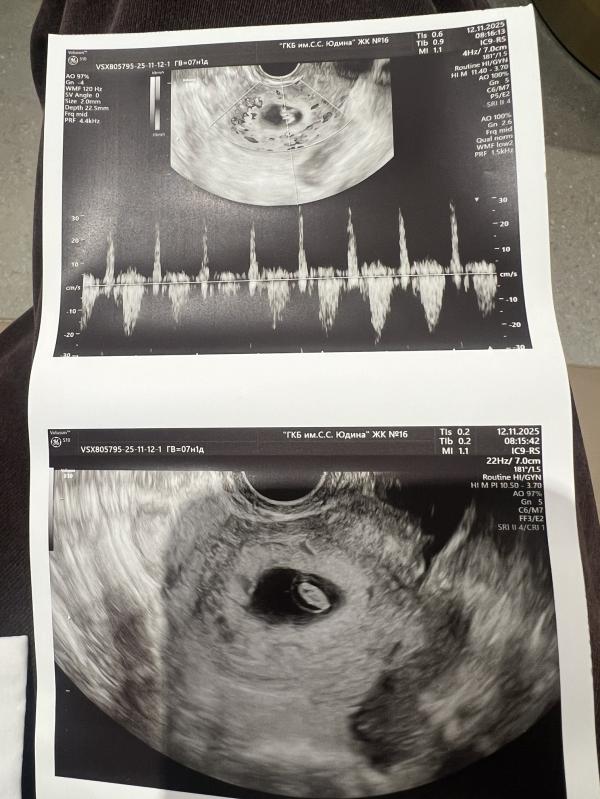

С одной стороны немного выдохнула, СБ есть, КТр правда написали как будто по среднему, даже не уверена что меряли его 😒 а вот длина шейки меня забеспокоила, 27 мм на 7,1 недель это как то совсем немного 😟😟😟 может ли такое быть что хотели написать 37 и ошиблись ?